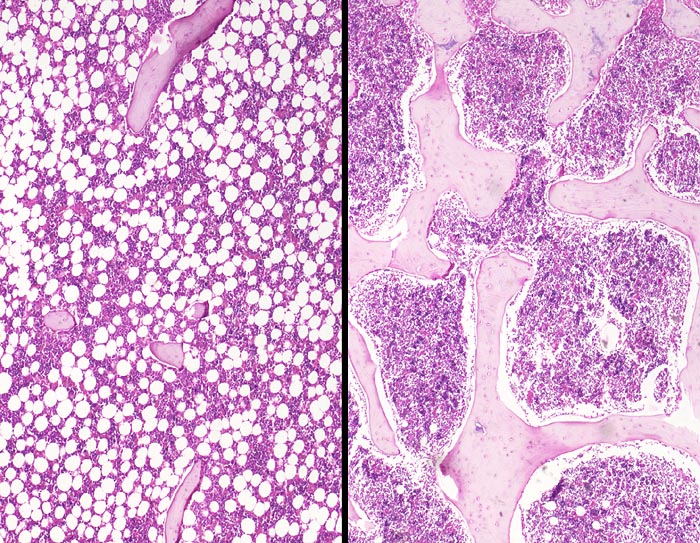

• Linker Wirbelkörper mit Osteoporose, rechts ein normaler Wirbelkörper zum Vergleich.

• Deutliche Rarefizierung und Atrophie vor allem der horizontalen Spongiosabälkchen.

• Hochgradige Reduktion der intertrabekulären Vernetzung.

• Reaktiv hyperplastisches blutbildendes Mark.